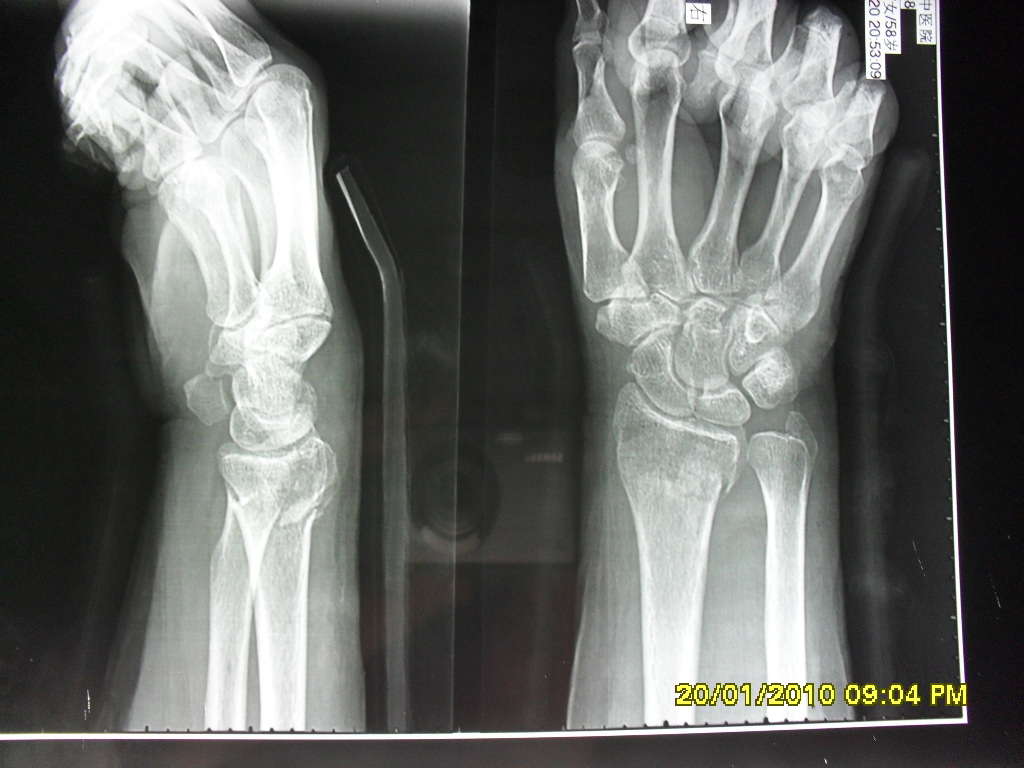

科雷氏骨折

桡骨远端骨折为最常见的骨折之一,它包括科雷骨折(colle′s fracture)

科雷骨折畸形愈合,严重者桡骨下端关节面极度背倾,桡骨短缩,下尺桡